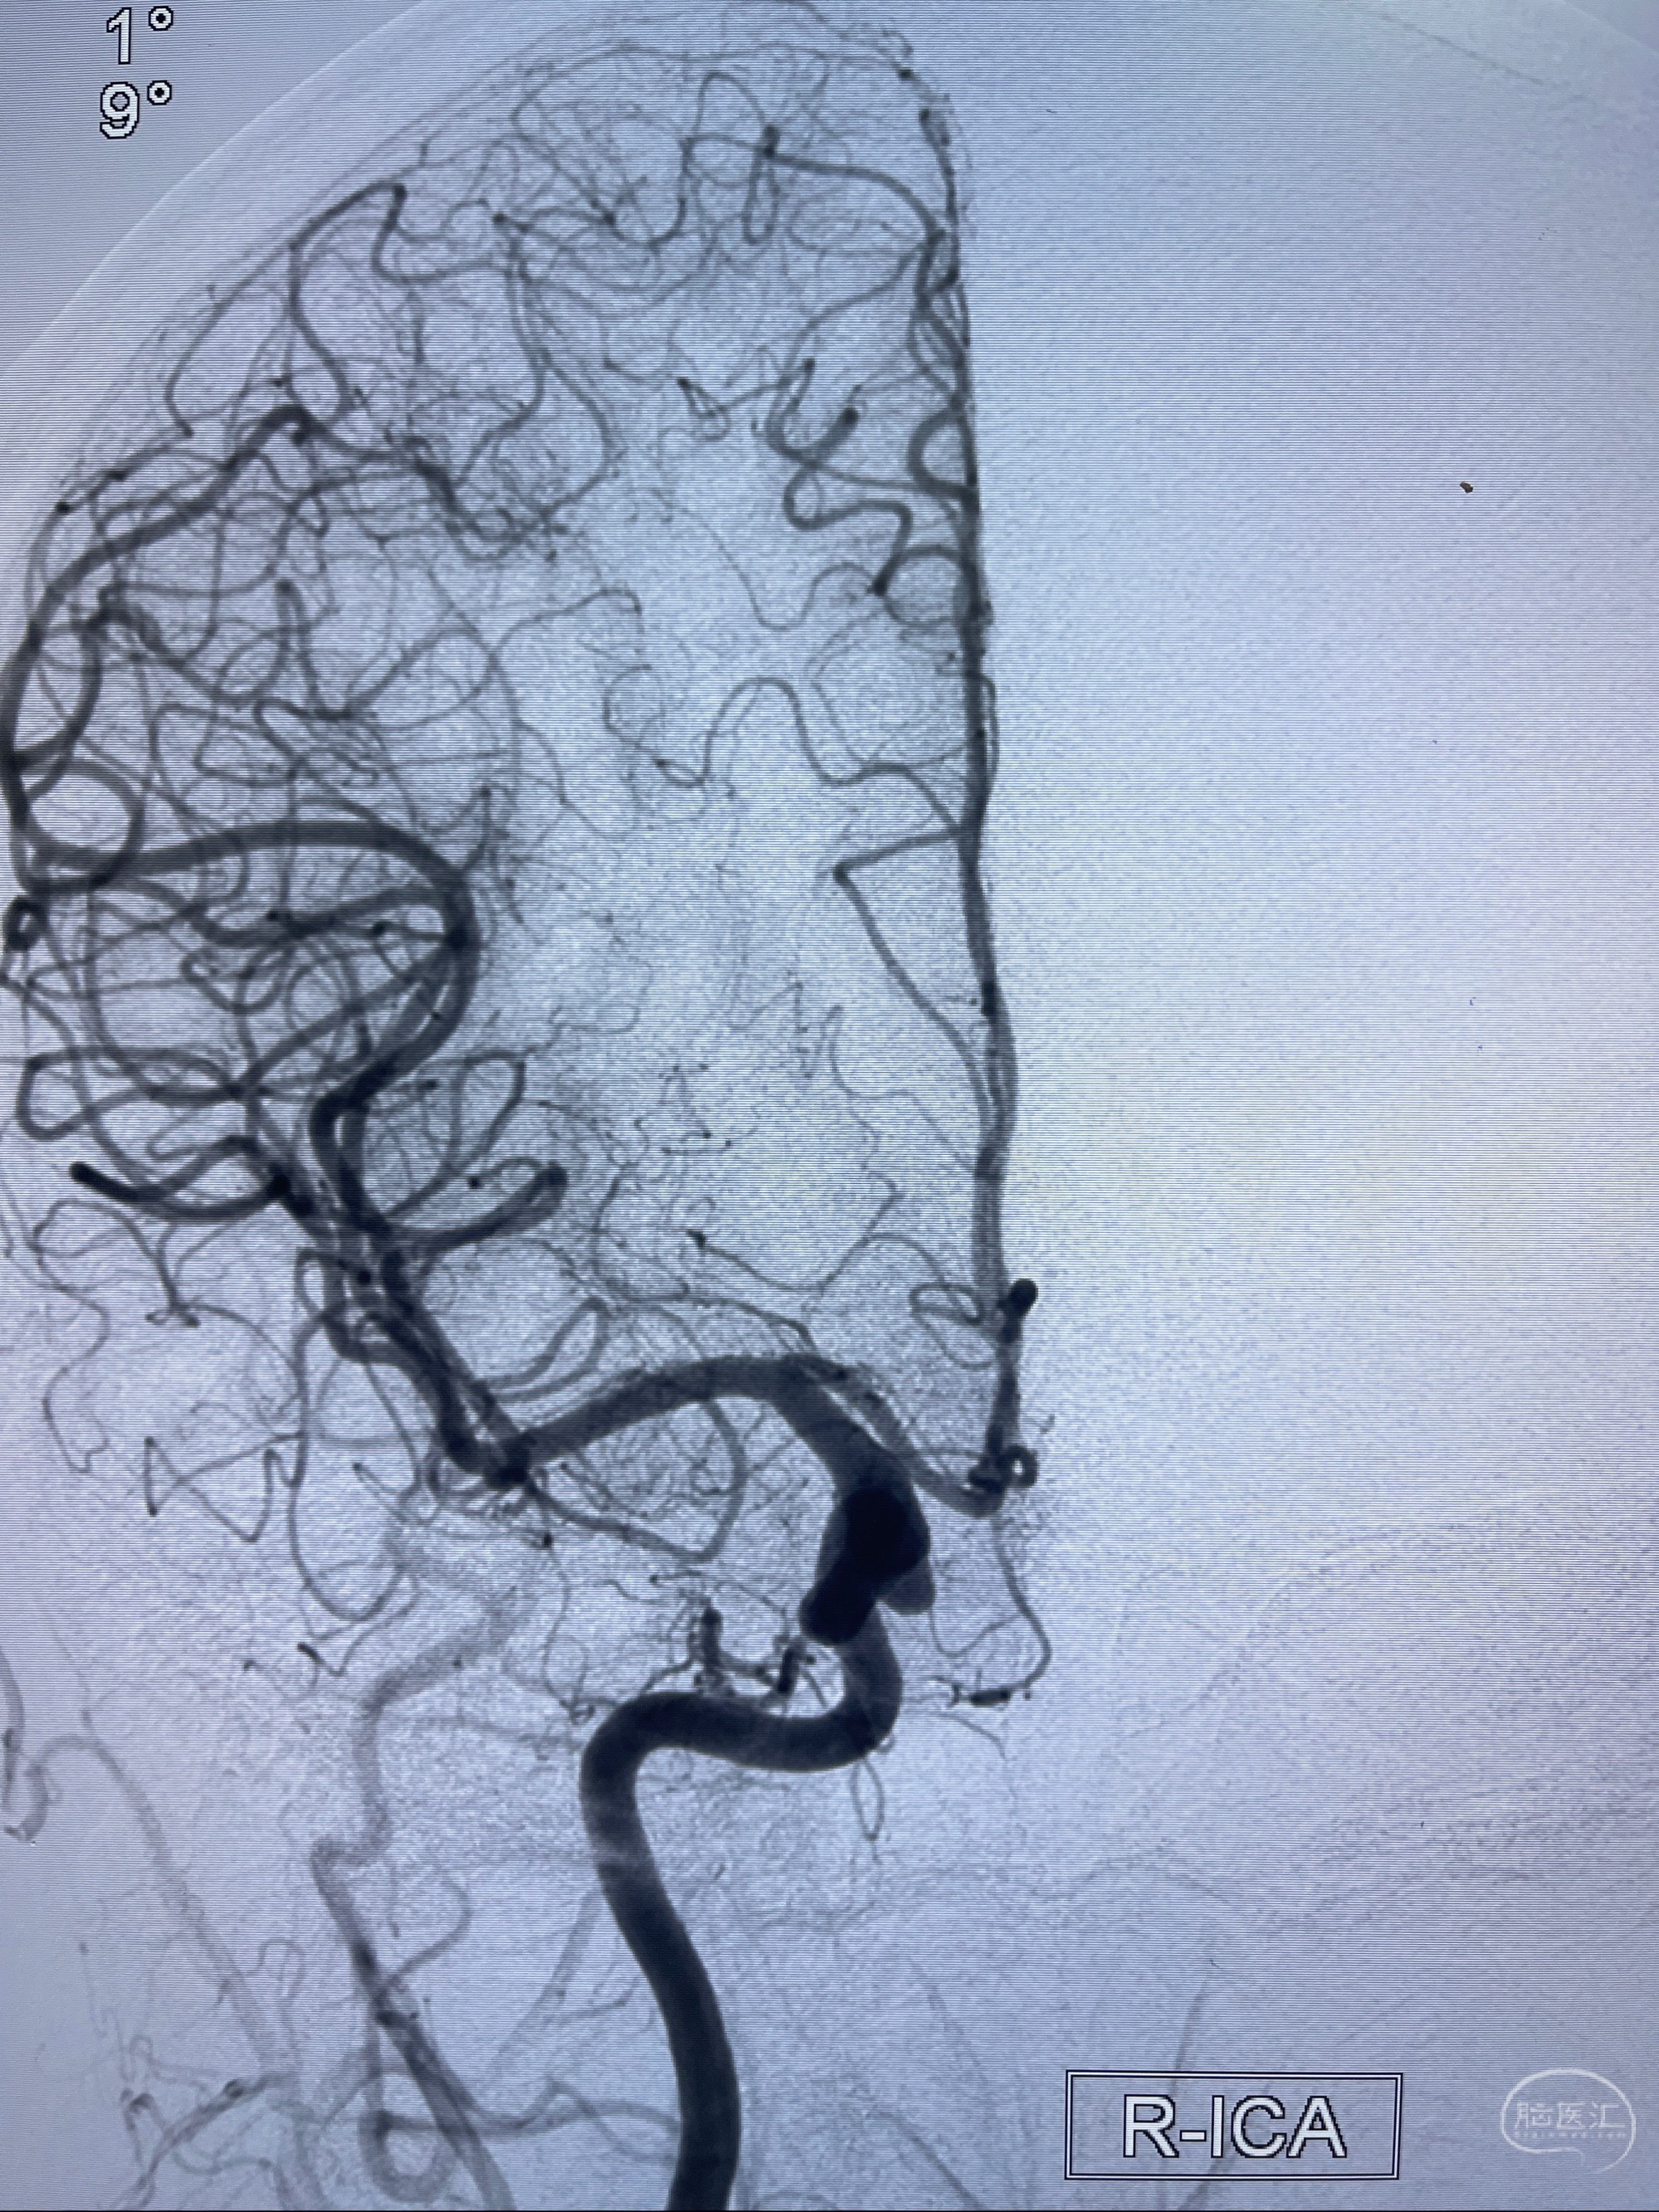

1.右侧颈内动脉眼动脉段动脉瘤

2023-07-27全脑血管造影:双侧颈内动脉眼动脉段动脉瘤,右侧较大

2023-08-01全麻下行双侧颈眼动脉瘤支架辅助栓塞